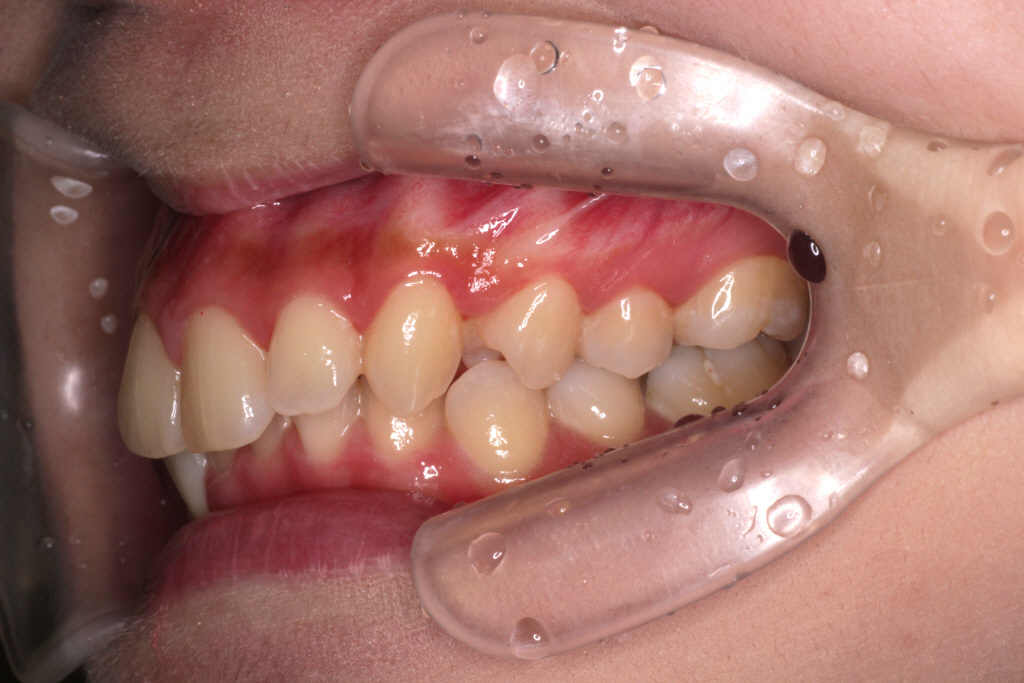

↓お口の中の状態です。

⑴深かった咬み合わせがしっかりと改善されました。

⑵右下の2番目の歯のずれも治りました。

⑶右上の2番目の歯の咬み合わせがよくなりました。

⑷正中も綺麗に合いました。

これで気になるところが改善されたので矯正は終了です。